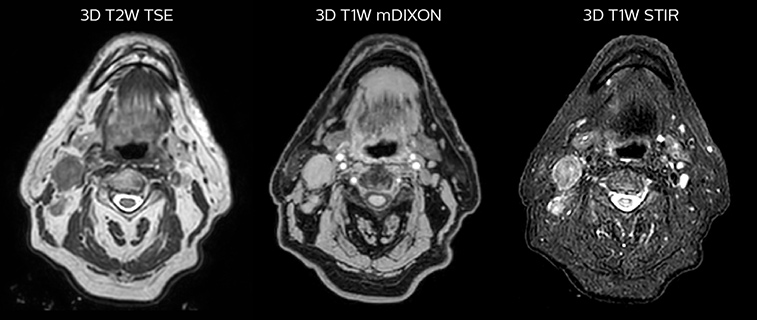

Epidermoid carcinoma of the left tongue base

The patient was diagnosed with an epidermoid carcinoma of the base of the left invading the amygdala lodge and the amygdaloglossal groove. Radiochemotherapy with curative aim was prescribed with a dose of 70 Gy for the tumor, 66 Gy on the suspicious nodes and 56 Gy on the elective drainage areas - in 33 fractions.

Simulation imaging

LaTour 3D Stir mDIXON MRI scans

T2W 3D, 3D STIR and mDIXON MRI scans.

Comparison of CT simulation scan

Comparison of CT simulation scan (left) and T2W 3D MRI (right)